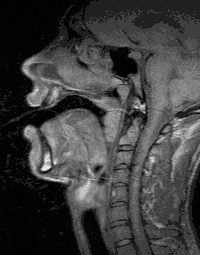

A toldalékcső

A toldalékcső beszédműködés közben

A garatüreg a légjáratnak a gégefő felett való közvetlen folytatása. Itt dől el, hogy a levegő az orrüreg vagy a szájüreg felé tart: az ínyvitorla vagy ínycsap szabályozza a levegő útját. Ha a szájüreg felé elzárja a levegő útját, az orrüregen át távozik, és orrhangok jönnek létre (m, n, ny), ha az orrüreg felé zárja a kiáramlást, szájhangok keletkeznek. A magánhangzók és mássalhangzók többsége ez utóbbi módon jön létre, illetve módosul.

A szájüregben a beszédhangok képzése szempontjából rendkívül fontos szervpár a nyelv és a szájpadlás. A szájüregnek kétféle szerepe van: hangmódosító és hangforrás. Alakját és térfogatát főképp a nyelvmozgás szabályozza. A nyelv nyugalmi helyzetből való elmozdulása kétirányú lehet: emelkedik függőleges síkban – a magánhangzók zártsági fokát határozza meg; másfelől előre-hátra mozog vízszintes síkban. Ha a nyelv egész tömege előrenyomul, kis hangszekrény keletkezik, és magas hangszínűvé teszi a zönge akusztikai hatását. Ha a nyelv hátrahúzódik, a nagyobb hangszekrény következtében mély hanghatásúvá válik a zönge. A hangmódosítási funkció a magánhangzók minőségi tulajdonságában meghatározó jegy.

A szájüreg hangforrás is lehet. Két szerv párt alkotva akadályt állít a kitóduló levegő útjába, s az akadályba ütközés, illetve annak legyőzése zörejt eredményez. A szájüreg artikulációs szervpárja a nyelv és a szájpadlás. A mássalhangzók akadályhangok, és képzésük helye többnyire a szájüreg.

A toldalékcső szemmel látható záró része a két ajak. Hangforrás, és hangmódosító rendeltetése is van, így a magán- és mássalhangzók minőségét meghatározó képzési jegy szerve. Az ajaknyitás alakja és nagysága a szájüreg térfogatát szabályozza, s ezzel hangmódosító szerepet tölt be. Alkothat akadályt is, melynek leküzdése beszédhangot hoz létre, azaz hangforrás.